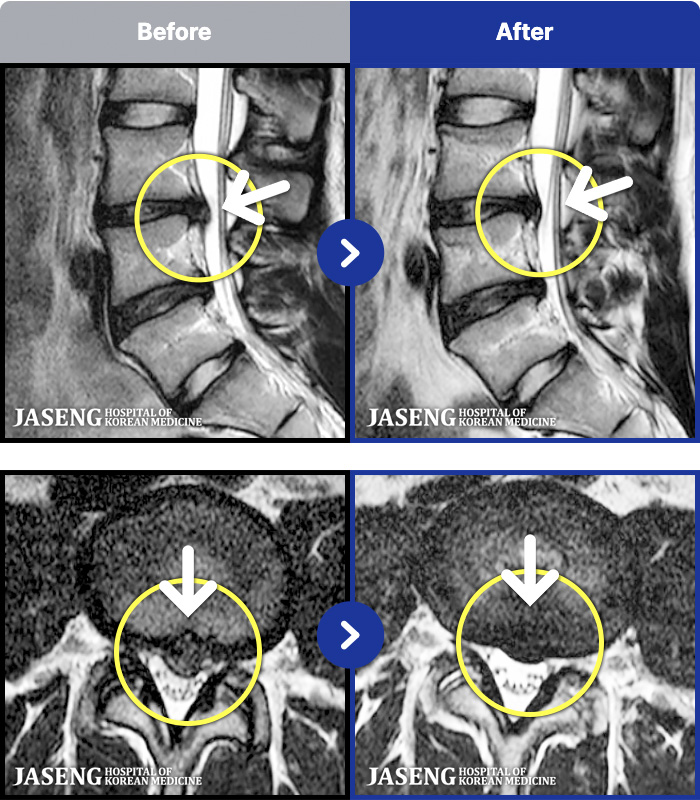

1,241 MRI ũ ʸ Ȯϼ.

MRI ġ

㸮, ٸ ٷ

ǿ

ȯ